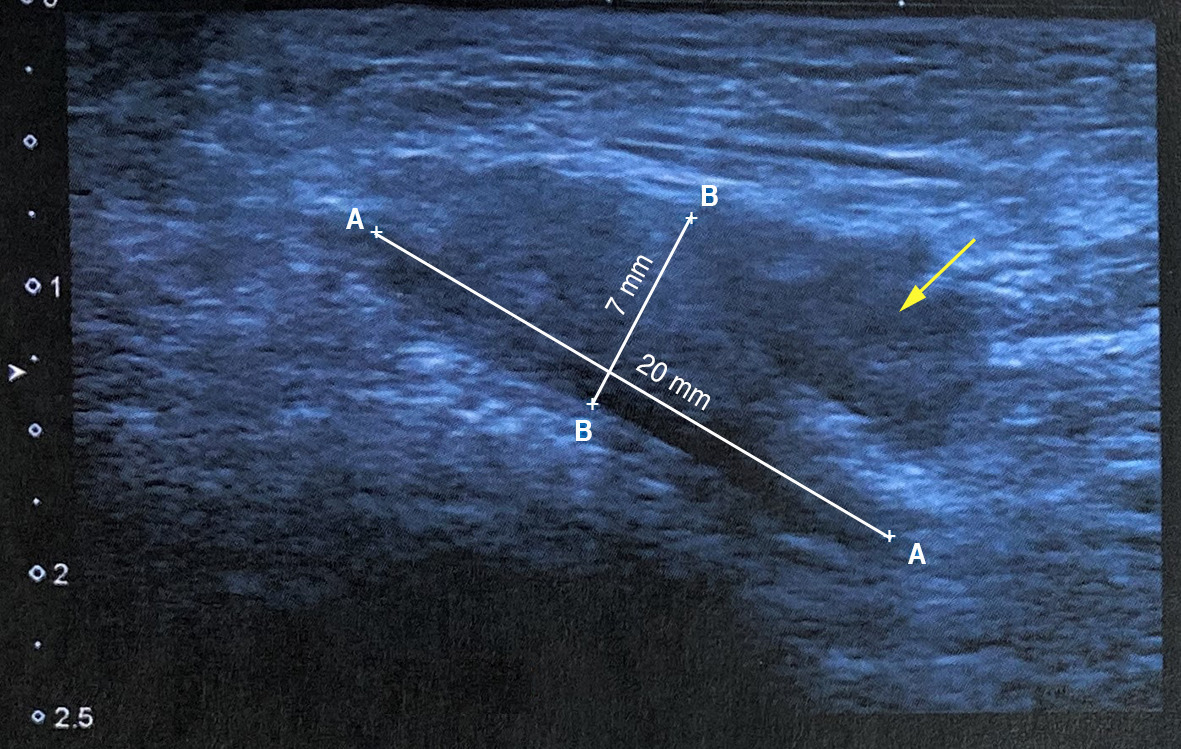

Le diagnostic est essentiellement clinique mais des examens d’imagerie peuvent être réalisés : échographie (figure)ou IRM, en cas de manifestations peu évocatrices.